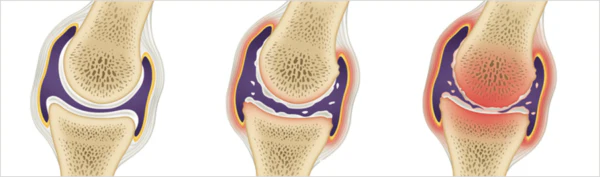

통풍은 주로 체내에 과다 축적된 요산으로 인해 발생합니다. 요산은 우리가 섭취하는 다양한 음식이 소화되어 최종적으로 대사된 후 혈액에 녹아 있다가 소변으로 배출되는 물질입니다. 일반적으로 혈액 내에서 요산은 정상 수준을 유지하며 배설됩니다. 그러나 통풍 환자는 혈액 내 요산이 과다하게 증가합니다. 이러한 과다 축적된 요산은 결정체로 변화하고, 이러한 결정체가 관절 내에 침착하여 염증을 일으킵니다.

통풍을 적절히 치료하지 않을 경우, 발작성 관절염의 빈도가 증가하고 침범하는 관절 수도 더 많아지며, 회복에 필요한 시간도 증가합니다. 반복적인 관절염은 관절을 점차 손상시키며, 만성적인 관절염으로 진행될 수 있습니다. 또한 통풍성 결절이라 불리는 덩어리가 관절 주위나 피부 조직에 나타날 수 있습니다. 이러한 결절은 요산 결정체의 덩어리로 어느 부분에서든 형성될 수 있으며, 주로 팔꿈치, 귀, 손가락, 발가락, 발목 등에서 발생할 수 있습니다. 때로는 요로 결석을 형성하기도 합니다.